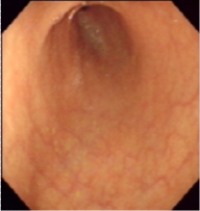

1.慢性浅表性胃炎又称慢性单纯性胃炎胃粘膜最常见的病变之一,中国国内胃镜检出率高达20%~40%,以胃窦部常见;胃镜见胃粘膜:胃粘膜充血、水肿,呈淡红色,可伴点状出血及糜烂,表面可有灰黄色或灰白色粘液渗出物覆盖;显微镜示:病变位于粘膜浅层; 2.慢性萎缩性胃炎根据发病是否与自身免疫有关及是否伴有恶性贫血,分为A、B型;A型属于自身免疫性疾病,患者抗壁细胞抗体(PCA)及抗内因子抗体(IFA)阳性,并伴有恶性贫血,病变主要位于胃体和胃底部;B型多见于胃窦部,无恶性贫血;两者胃粘膜改变相似;胃镜见胃粘膜:由正常的橘红色变为灰色或灰绿色,粘膜层变薄、皱襞变浅甚至消失、粘膜下血管透见,表面有细颗粒、偶见出血糜烂;显微镜可见淋巴细胞、浆细胞浸润、肠上皮化生、腺上皮化生、不典型增生;